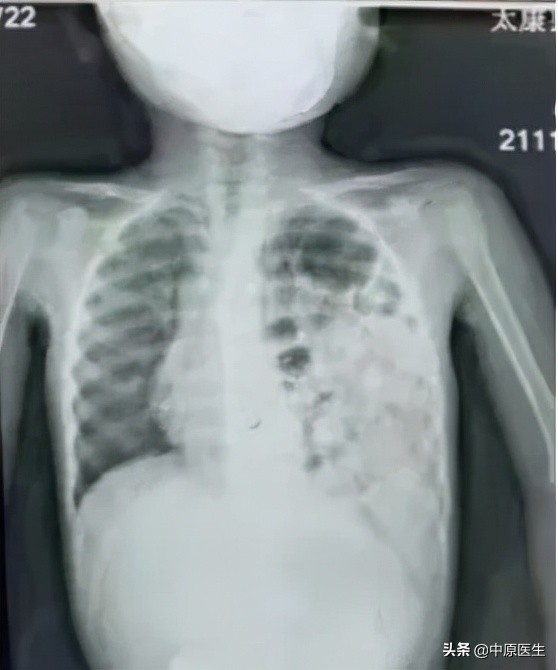

在河南省儿童医院胸心外科,程文哲医师诊断楠楠为先天性膈疝。影像资料显示,楠楠的左肺严重受压,如果继续压迫,左肺将失去功能甚至危及生命。

术前

术后在胸腔镜视野下,可看到楠楠的左侧胸腔内充满了胃和肠子,而左肺则受压变小,医生们帮助腹腔各脏器回到它们原本的位置,紧接着修补了缺损的膈肌,最后让受压的左肺重新膨开了。